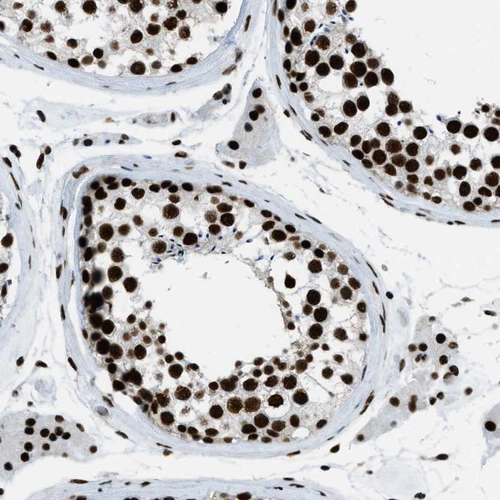

Immunohistochemical staining of human cerebral cortex, gastrointestinal, lymphoid tissues and testis using Anti-ZNF207 antibody HPA017013 (A) shows similar protein distribution across tissues to independent antibody HPA063908 (B).